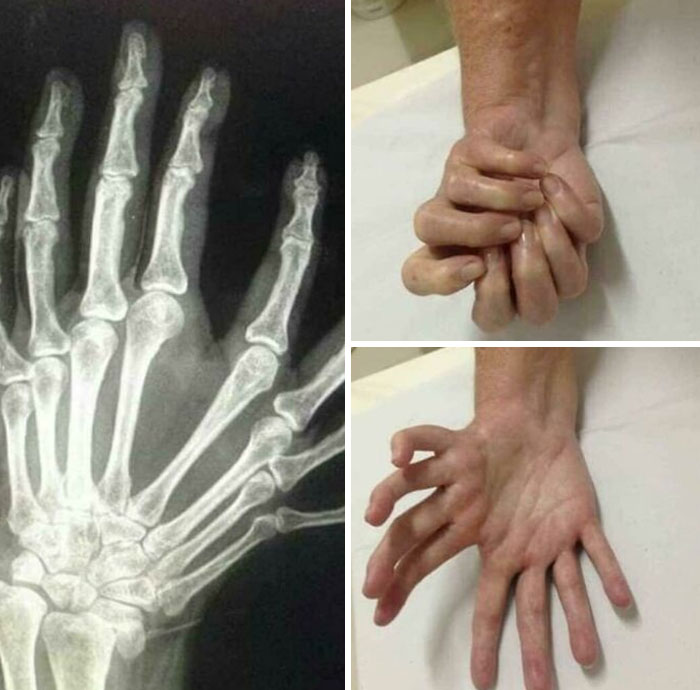

This Condition Is Called Mirror Hand Syndrome, Less Than 100 Cases Have Ever Been Diagnosed And The Cause Is Still Unknown

Genuine question, are all of the fingers usable? Can some medical Panda explain?